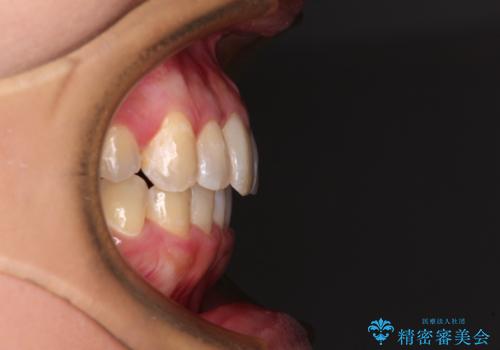

前歯のデコボコをインビザラインでスッキリと仕上げる

- 上下前歯のデコボコと奥歯の銀歯を気にして来院された患者様です。

口元をインビザラインにより歯列を整え、その後に失活している奥歯をオールセラミッククラウンにて補綴治療することとしました。

長時間のマウスピース装着に協力いただき、自然な口元に仕上げることができました。

気になっていた銀歯もオールセラミッククラウンで本物の歯のようになり、患者様には大変満足していただきました。